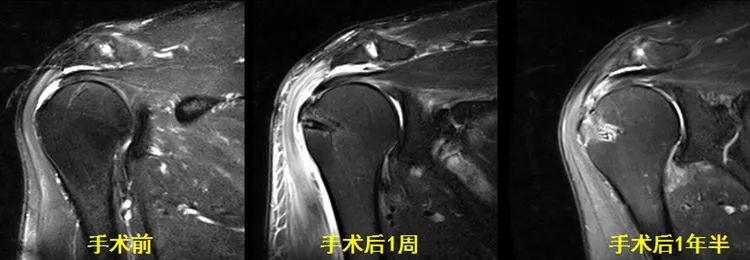

(6)正确评估手术后肩袖的改变

肩袖撕裂的手术在我国越来越普及,需要提醒的是肩袖撕裂术后不管愈合与否,肩袖的信号以及形态都不会正常!因此我们的阅片解读特别是书写MRI报告时都要极为小心,以避免不必要的纠纷。